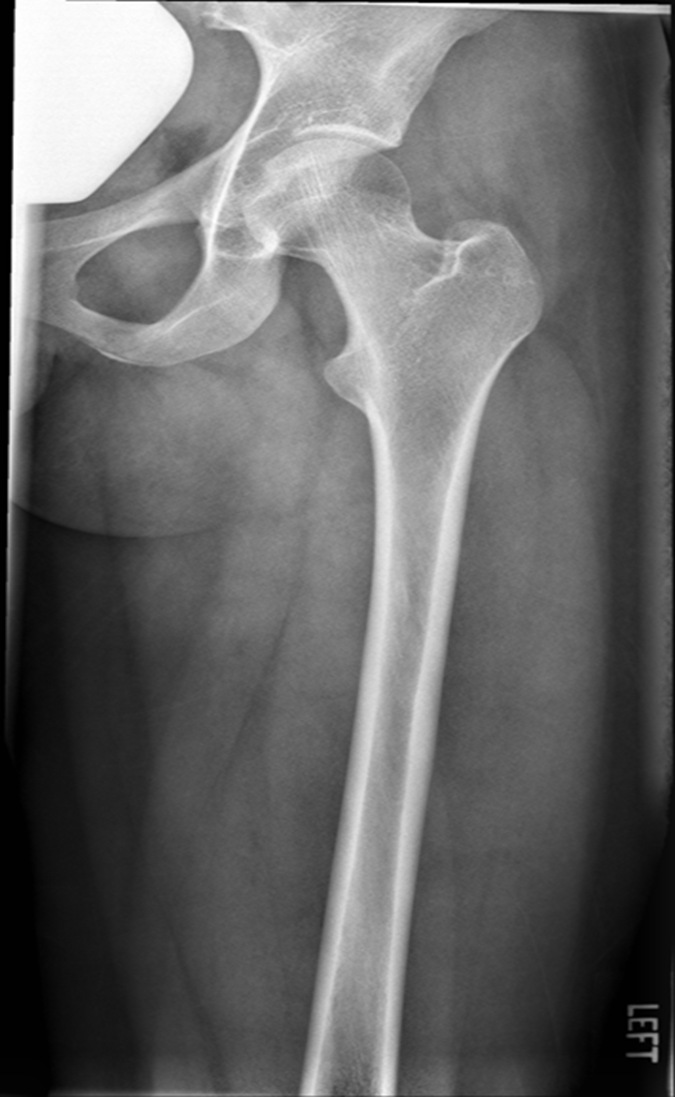

Lateral Femur

•Evidence of proper collimation and the presence of a side marker placed clear of the anatomy of interest

•Most of the femur and the joint nearest to the pathologic condition or site of injury (a second projection of the other joint is recommended)

•Any orthopedic appliance in its entirety

•Bony trabecular detail and surrounding soft tissues

•

With knee included (distal)

•Superimposed anterior surface of the femoral condyles

•Patella in profile

•Open patellofemoral space

•Inferior surface of the femoral condyles not superimposed because of divergent rays

With the hip included (proximal)

•Opposite thigh not over proximal femur and hip joint

•Greater trochanter superimposed over distal femoral neck

•Lesser trochanter visible on medial aspect of proximal femur

Under-rotated, sticking out laterally REPEAT, place marker bottom of light field

Can not see e lesser trochanter, can not see the greater trochanter sticking out laterally, OVER ROTATED can not see lesser

Under rotated, prominent lesser trochanter, femur is not parallel, not fully lateral, wide collimation

REPEAT under rotation

Condyle is coming into patellafemoral joint space, condyle coming down and infront, ROTATION, medial condye is inferior, medial condyle is towards patella, over-rotation

fibula is popping out back

Not enough anatomy, under exposed, medial is pretty aligned, no rotation on image, increasing technique move central ray distally.